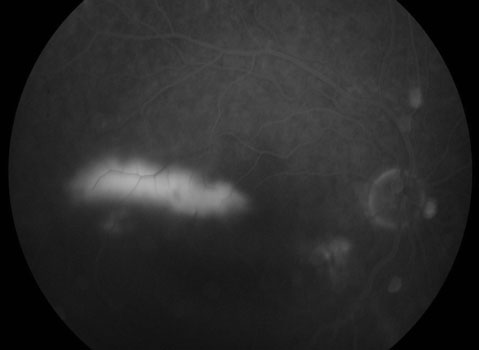

CSR with Smokestack Leak

You can’t diagnose CSR by looking in the mirror since your eye will usually look and feel normal. The diagnosis is made with a thorough retinal examination through a dilated pupil, along with OCT scanning and fluorescein angiography. Angiography is helpful in confirming the diagnosis, as well as in identifying the leak when contemplating treatment.